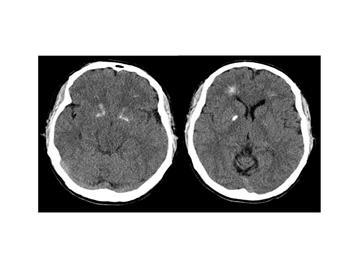

Рис. 9 Компьютерная томограмма мозга пациента с делецией

Описание: 447